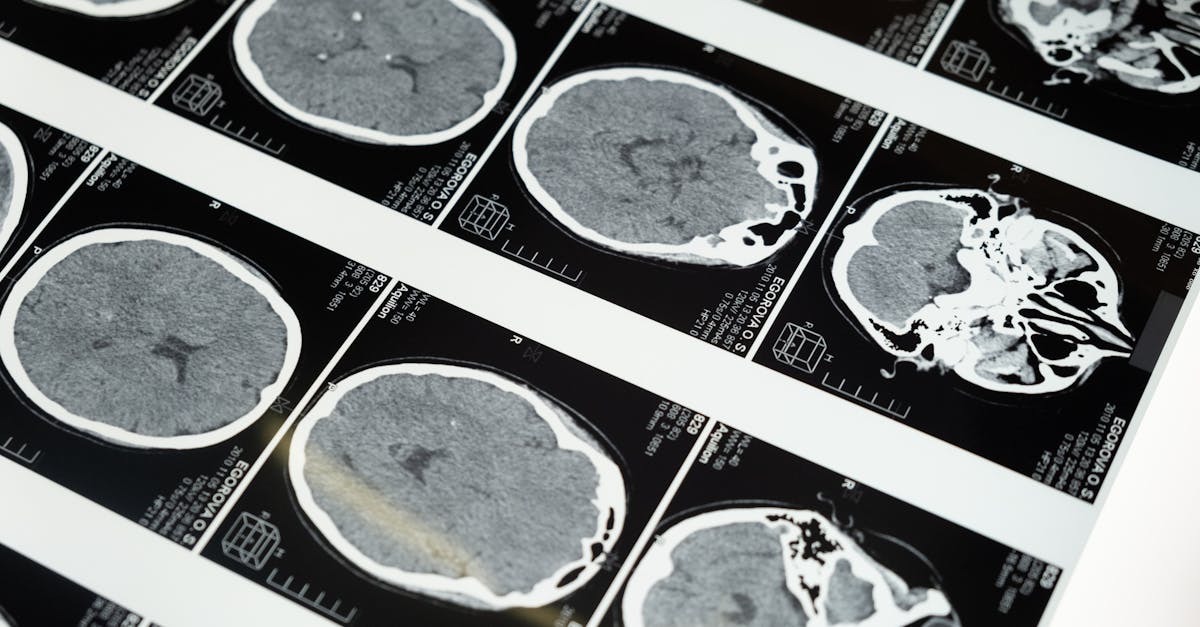

Medical imaging plays a crucial role in the diagnosis and treatment of various medical conditions. One of the key advantages of medical imaging is its ability to provide detailed insights into the internal structures of the body. Through techniques such as X-rays, MRI, CT scans, and ultrasound, healthcare professionals can visualize organs, tissues, and bones to detect abnormalities or diseases.

Medical imaging plays a crucial role in enhancing patient care by providing healthcare providers with valuable insights into the patient's condition. By utilizing various imaging techniques such as X-rays, CT scans, MRIs, and ultrasounds, healthcare professionals can accurately diagnose diseases and injuries, leading to better treatment outcomes. Through medical imaging, doctors can identify abnormalities within the body, assess the progression of diseases, and plan appropriate interventions tailored to the individual needs of each patient.